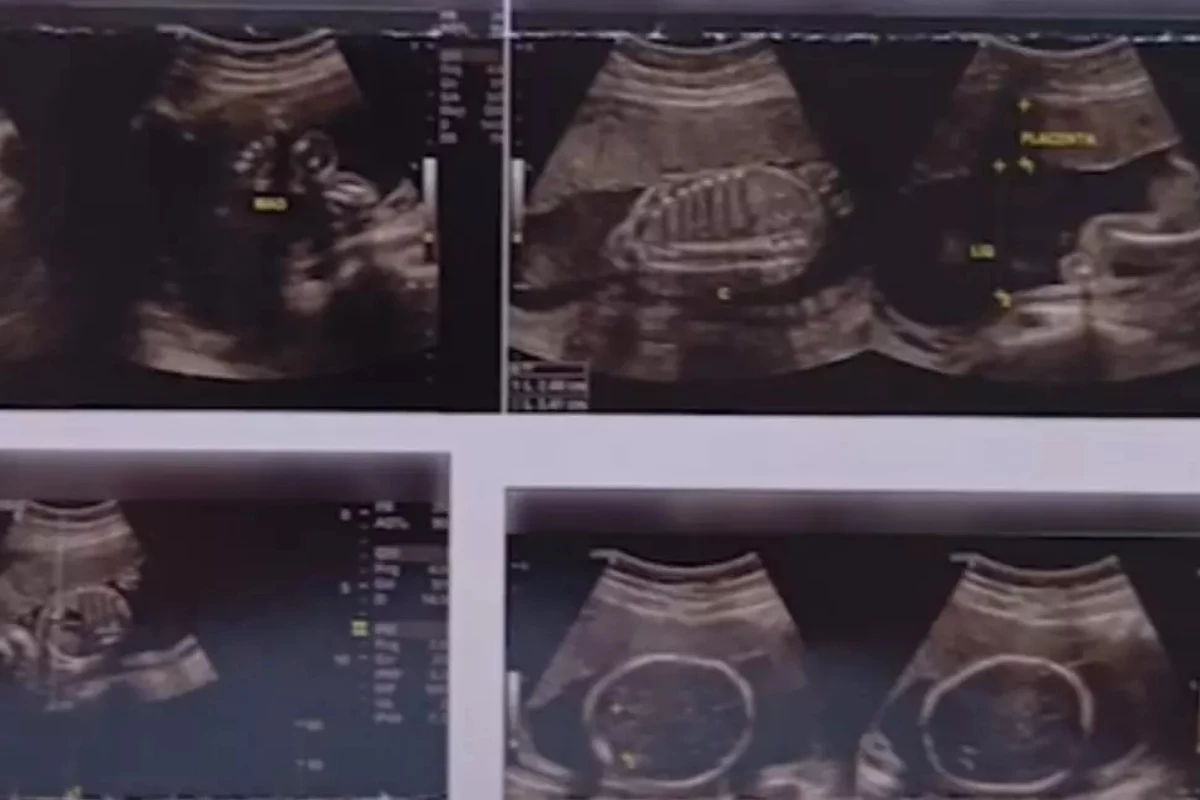

Homem recebe diagnostico de gravidez após ultrassom em clínica no Paraná: ‘consta meu nome, tudo certinho’

O homem foi surpreendido ao ver a existência de um bebê no que seria a própria barriga.

A situação foi registrada e divulgada por Eluciana Íris Almeida Cardoso, de 54 anos.